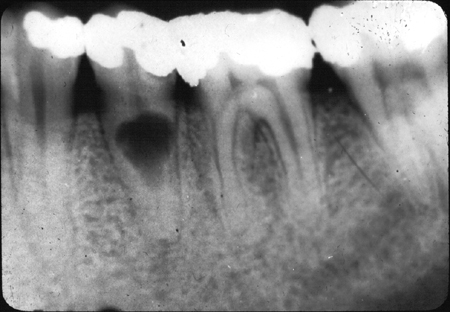

- Radiological:

- Short, blunt roots

- Partial/ total obliteration of pulp chamber & root canal by dentine

- X-ray: Short roots & obliterated pulp

- X-ray: Enlarged pulp chambers

- X-ray:

- Ghost teeth

- Decreased radiopacity

- Loss of distinction between enamel and dentine